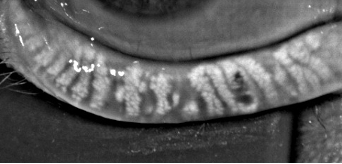

I’ve spent hours poring through the literature, and even searched through Eastern medicine for anything promising, with little success. See those horrific glands in the photos below? Those are mine, imaged on July 31st. Awful, right? And that’s after numerous rounds of intense pulsed laser (IPL) therapy, regular use of heat masks, and taking various supplements designed for dry eye disease.